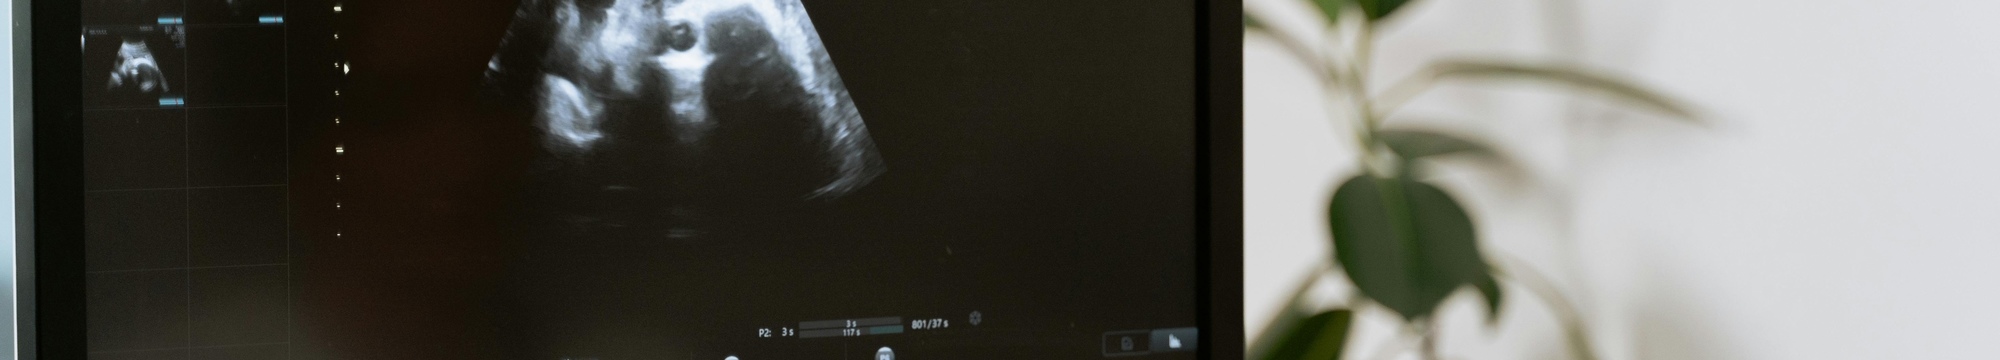

This case describes a 24-year-old primigravida woman from a rural area in Santander, Colombia, who began prenatal care late at 28.3 weeks. At 29.3 weeks, obstetric ultrasound showed hypoplasia of the cerebellar vermis and an enlarged cisterna magna, later confirmed by neurosonography and fetal magnetic resonance as a Dandy-Walker spectrum variant. Congenital infections were ruled out, and the mother declined invasive genetic testing. At 39 weeks, a cesarean section was performed, and the male newborn had adequate neonatal adaptation. Postnatal cranial ultrasound revealed a cystic dilation suggestive of a Dandy-Walker variant or Blake’s pouch cyst. Outpatient follow-up was not possible. This case highlights how limited access to healthcare in rural areas can delay prenatal diagnosis and restrict a comprehensive approach, although some variants may have a benign neonatal course. Strengthening prenatal care access is essential for timely and adequate management.